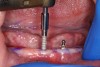

A sterile operating environment was established. Prior to administering anesthesia the location of the mental foramen and the exiting neurovascular bundle was established by palpating the facial aspect of the mandible; this procedure was performed in conjunction with the cross-sectional CBCT imaging. If this technique is inadequate, a radiographic splint can be used to further verify the position of the mental foramen; often, a patient’s existing mandibular denture can be modified for this purpose. A surgical marker was used to mark the proposed implant positions with at least 3-mm inter-implant spacing (Figure 2). Establishing the position of the mental nerve prior to administering local anesthesia is necessary, because the injection site will become filled with anesthetic solution, and/or submucosal hematoma will interfere with accurate palpation. Sufficient pain control was achieved via infiltration of local anesthetic in the area of the mental foramen as well as along the crest of the anterior mandible. Care was taken to minimize the patient’s exposure to epinephrine.

Fig 2. Preoperative view of mandible with proposed implant locations marked.

Figure 2